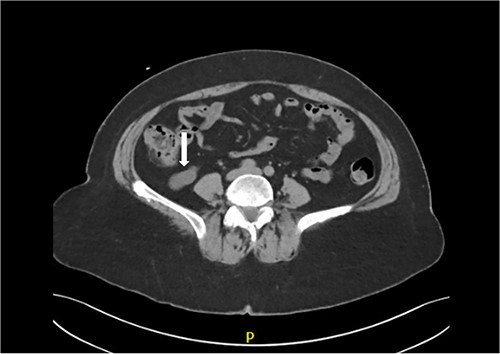

Abdominal and pelvis unenhanced CT scan was performed, which showed no signs of renal or ureteric calculi. No hydronephrosis was present. A 2.4 cm simple cyst was detected in the right kidney. No other significant renal abnormalities were present. Incidentally, a distended retrocecal appendix was identified suggestive of a mucocele (Fig. 1). Accordingly, underlying neoplastic process needed to be excluded. No free gas or fluid was found in the peritoneal cavity and other intraabdominal organs and lymph nodes were unremarkable.

CT scan shows markedly dilated appendix consistent with mucocele.